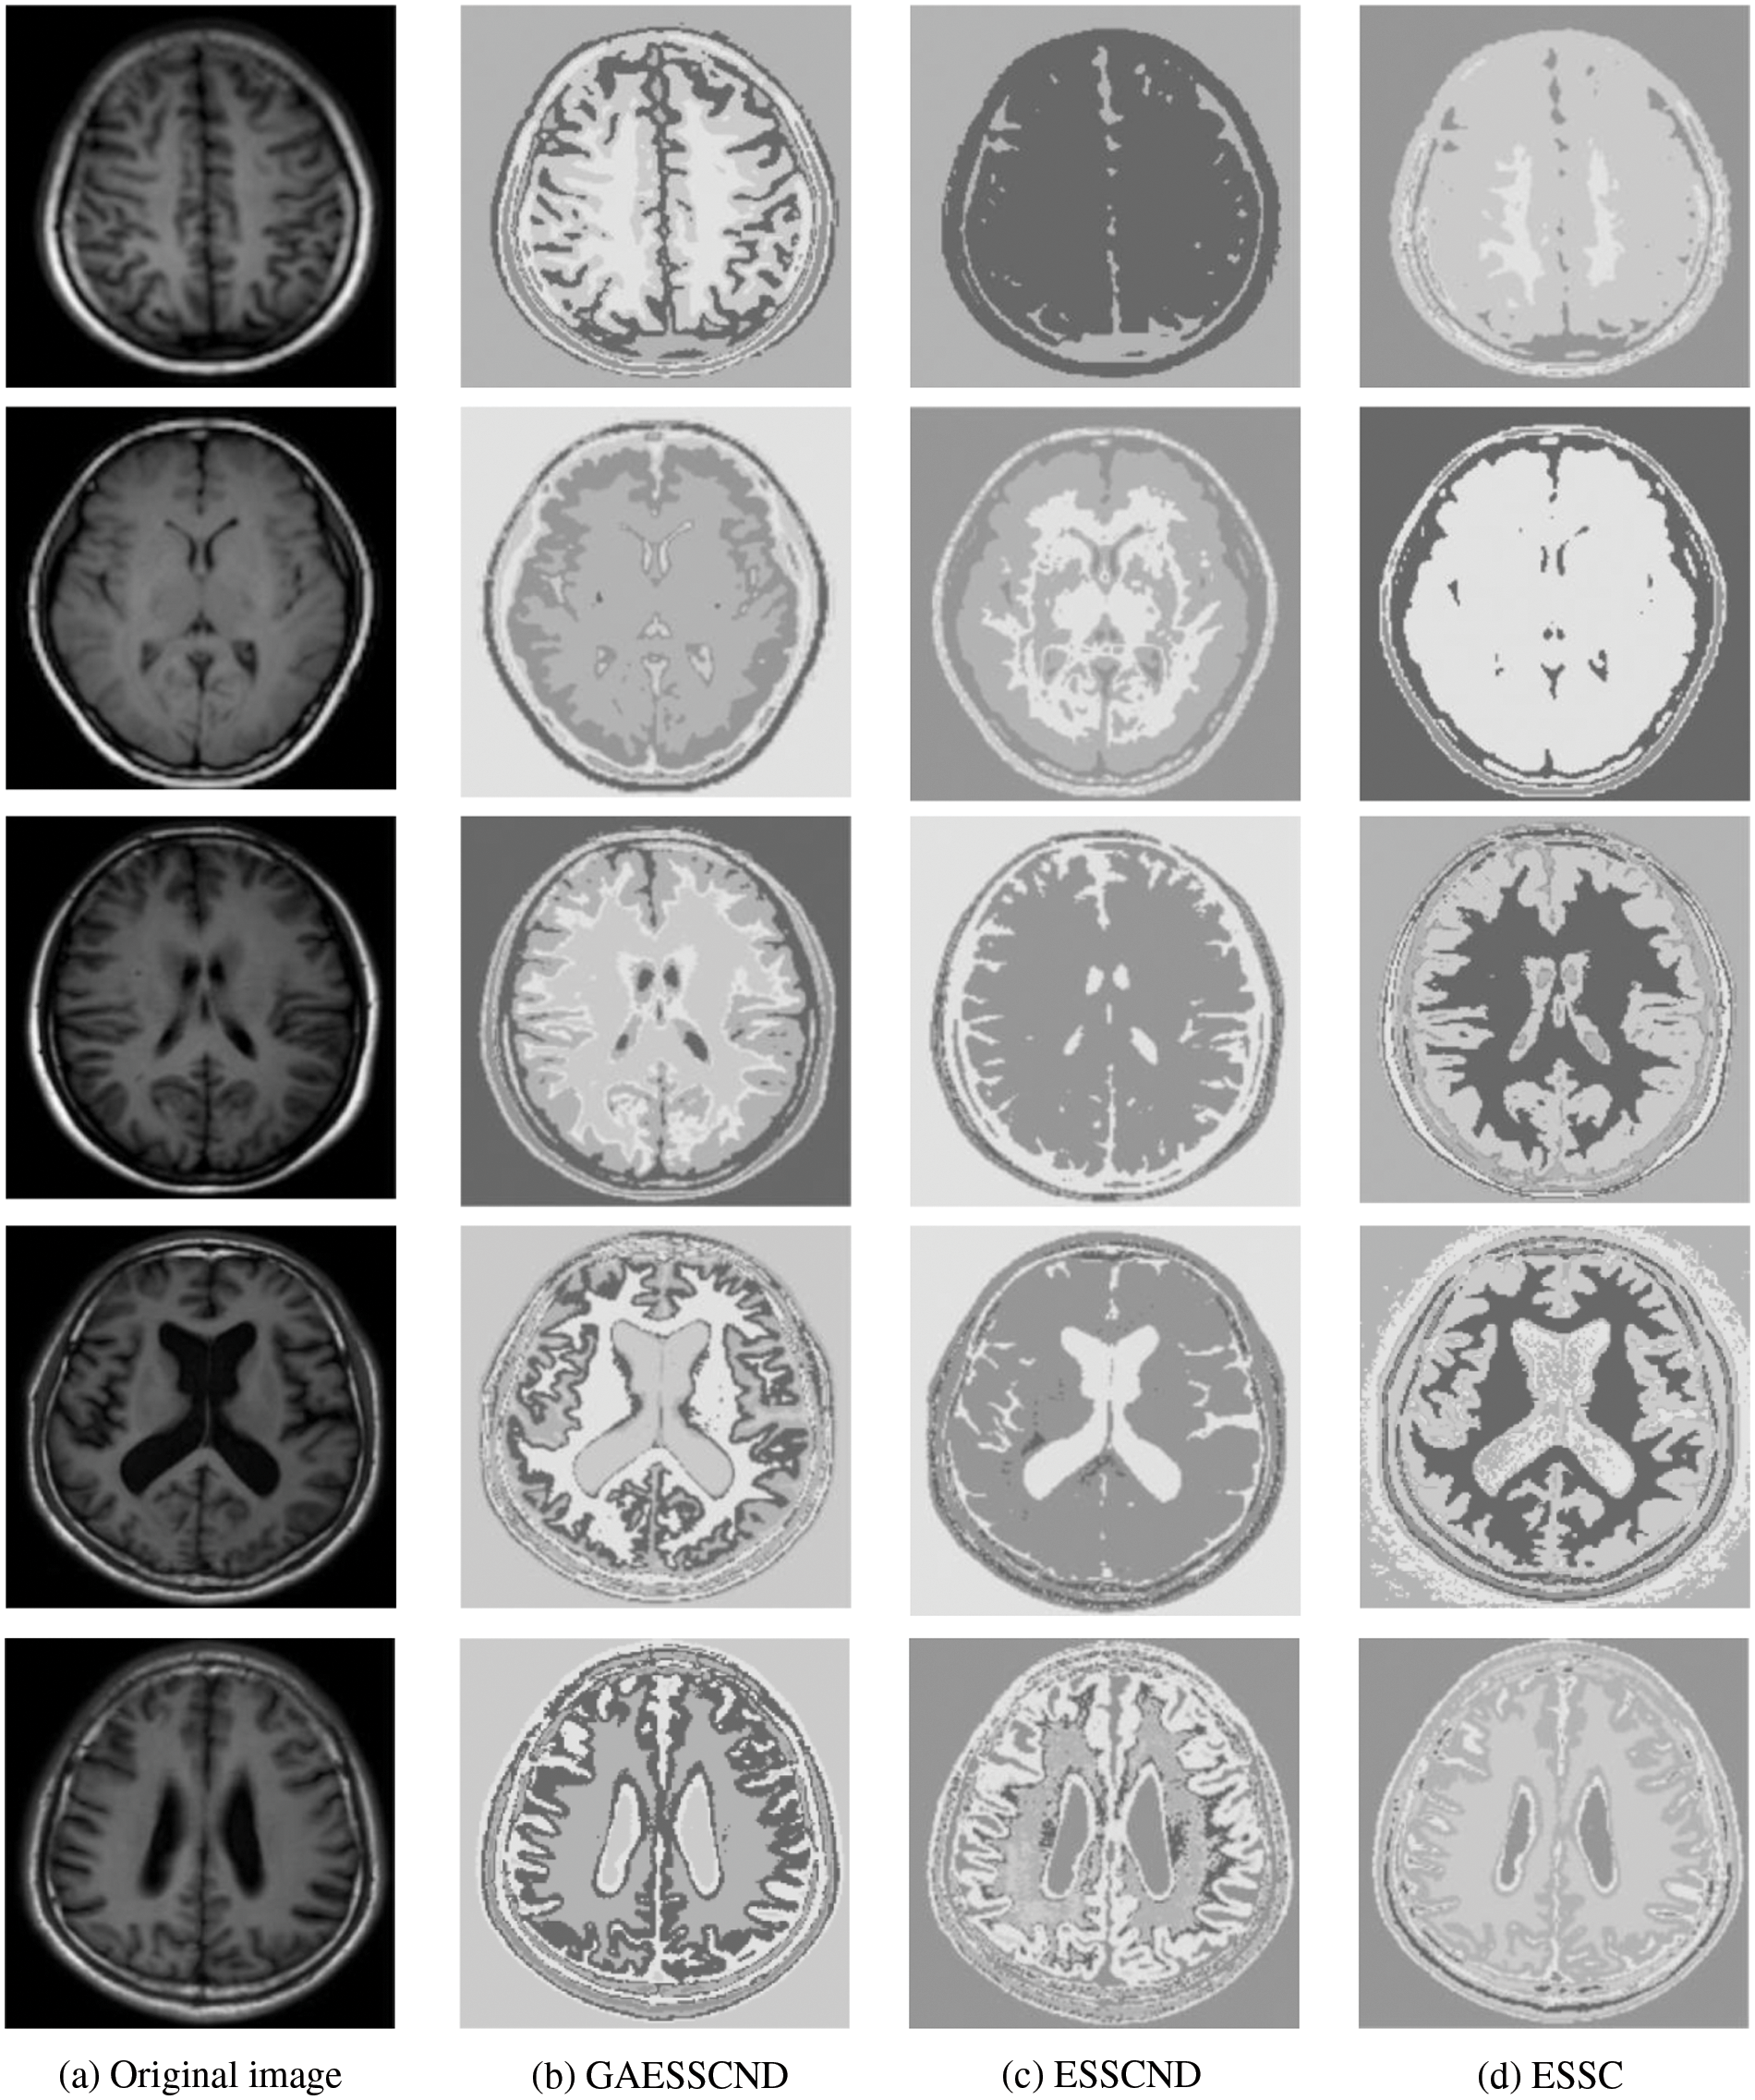

Taking the normal brain database as an example, multiple noise levels were provided, and the noise level pn0 = 0%, 1%, 3%, 5%, 7%, 9%. To verify the anti-noise performance of the algorithm, the highest noise level was selected, and 5 brain images were selected to verify the segmentation effect of the algorithm compared with other soft subspace clustering algorithms. The mode = T1, protocol = ICBM, phantom name = normal, section thickness = 1 mm, noise = 9%, and INU = 0%; brain images of 62 pages, 75 pages, 83 pages, 96 pages, 107 pages were selected. Cluster segmentation was performed for 0 = Background, 1 = CSF, Cerebrospinal Fluid, 2 = Gray Matter, and 3 = White Matter. The effect of segmentation and clustering is shown in Fig. 3:

Figure 3: The segmentation result of the T1-weighted simulated brain MR image, (a) depicts the original image, (b) depicts the standard segmentation result graph for evaluation calculation, (c) depicts the segmentation effect of the GAESSCND algorithm proposed in this paper, (d) depicts the segmentation effect of the ESSCND algorithm, (e) depicts the segmentation effect of the ESSC algorithm, (f) depicts the segmentation effect of the KESSC algorithm that guides the kernel function, (g) depicts the segmentation effect of the FSC algorithm, and (h) depicts the segmentation effect of the entropy weighted EWKM algorithm

In Fig. 3, Column (a) is the clustering algorithm proposed in this paper, and the segmentation effect is obviously better than that of other soft subspace clustering algorithms (b–h). In this chapter, the Rand Index (RI) [45], normalized mutual information (NMI) [46] and accuracy indices are used to evaluate the clustering effect, where RI and NMI are calculated by Eqs. (16) and (17), respectively.

Comparing the data obtained from Table 2, the segmentation effect of the GAESSCND algorithm is very similar to the standard segmentation. The GAESSCND algorithm proposed in this section is compared with four existing soft subspace clustering algorithms, ESSC, EWKM, FSC, and KESSC with a kernel function, and ESSCND with generalized noise detection, where the FSC algorithm is a fuzzy weighted soft subspace clustering algorithm and the EWKM algorithm is an entropy weighted soft subspace clustering algorithm. The ESSC algorithm combines intraclass and interclass information, and the rest of the improved soft subspace clustering algorithms select reasonable parameters in a larger range. The evaluation indices are chosen in 3 ways to determine the noise immunity of the GAESSCND algorithm for noisy MR images. From the displayed visual effect and the 3 evaluation indices, GAESSCND has good noise immunity, and the clustering effect is similar to the standard segmentation. Compared with other soft subspace clustering algorithms, which are not effective in segmenting boundaries and dividing brain regions, the GAESSCND algorithm can clearly divide brain white matter, brain gray matter, cerebrospinal fluid [47] and background regions well so that the problem of noise in MR images of the brain can be handled well.